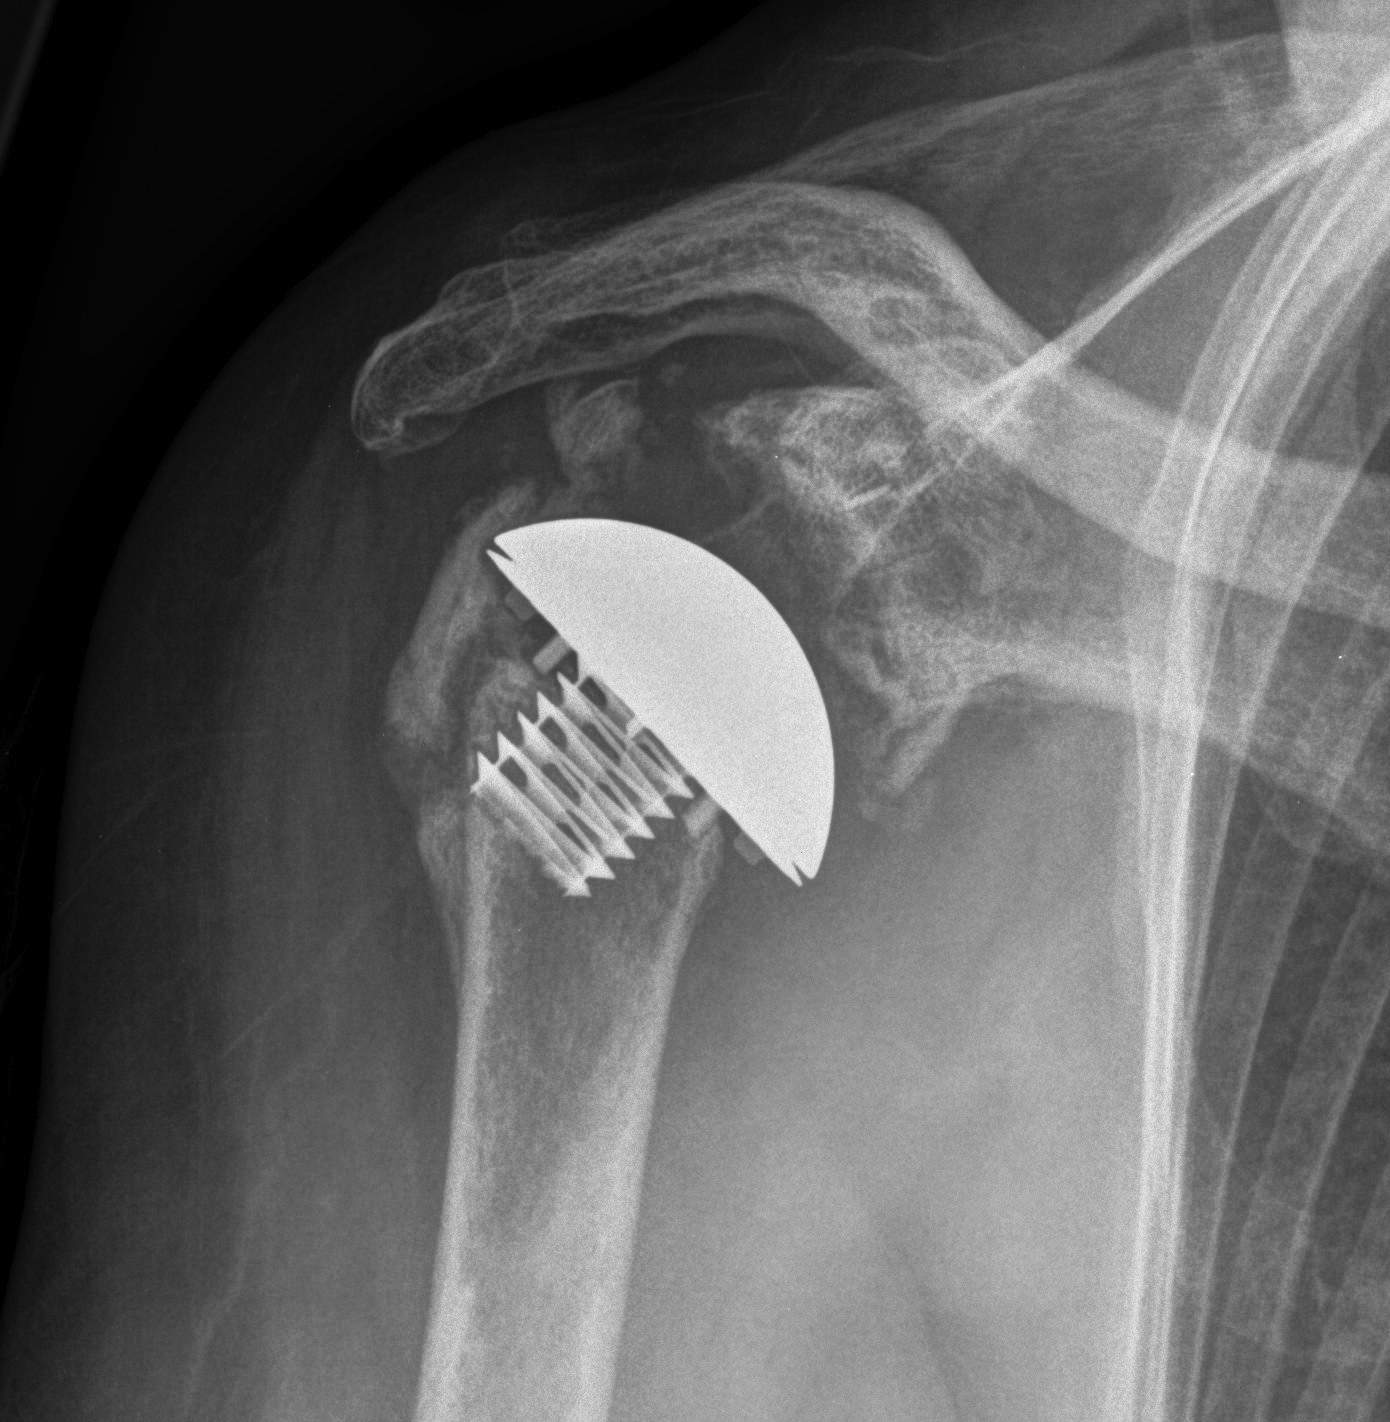

Peri-prosthetic Fracture

Cause

1.  Trauma

2.  Atraumatic - stress riser / loosening

Wright and Cofield Classification

Cofield Classfication

A:  Fracture centred at the tip and extends proximally greater than 1/3

B:  Fracture at tip only

C:  Fracture distal to tip of the prosthesis and extends into distal metaphysis

Options Humeral Shaft Fracture

A.  Non operative Management

- well-fixed prosthesis

- acceptable alignment

TSR Periprosthetic FractureTSR Periprosthetic Fracture

B.  ORIF

- displaced tuberosity fractures

- well-fixed prosthesis and fracture distal to prosthesis

Anterolateral approach and plate

C.  Revision

- loose humeral prosthesis / osteolysis

Long stem > 2 cortical diameters past fracture

aTSA fracture 1aTSA fracture 2revTSA following fracturerevTSA for fracture